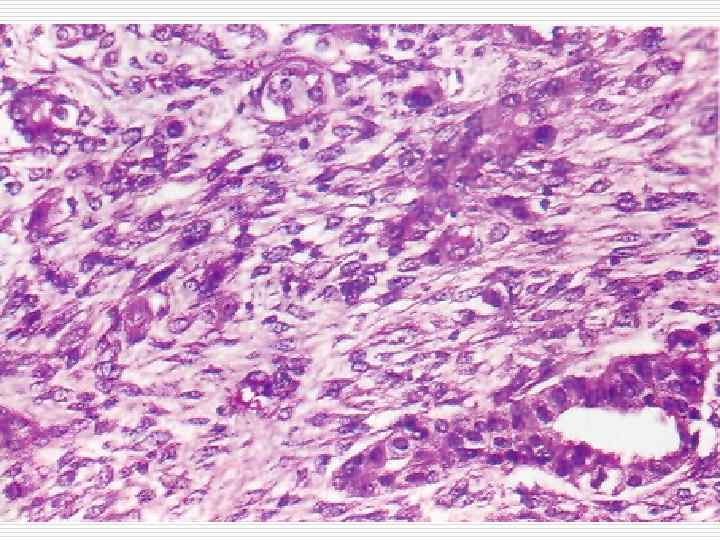

Squamous cell carcinoma

Tumors from the squamous and transitional epithelium o o Benign - papilloma Malignant – squamous cell keratinous and nonkeratinous carcinoma or transitional carcinoma.